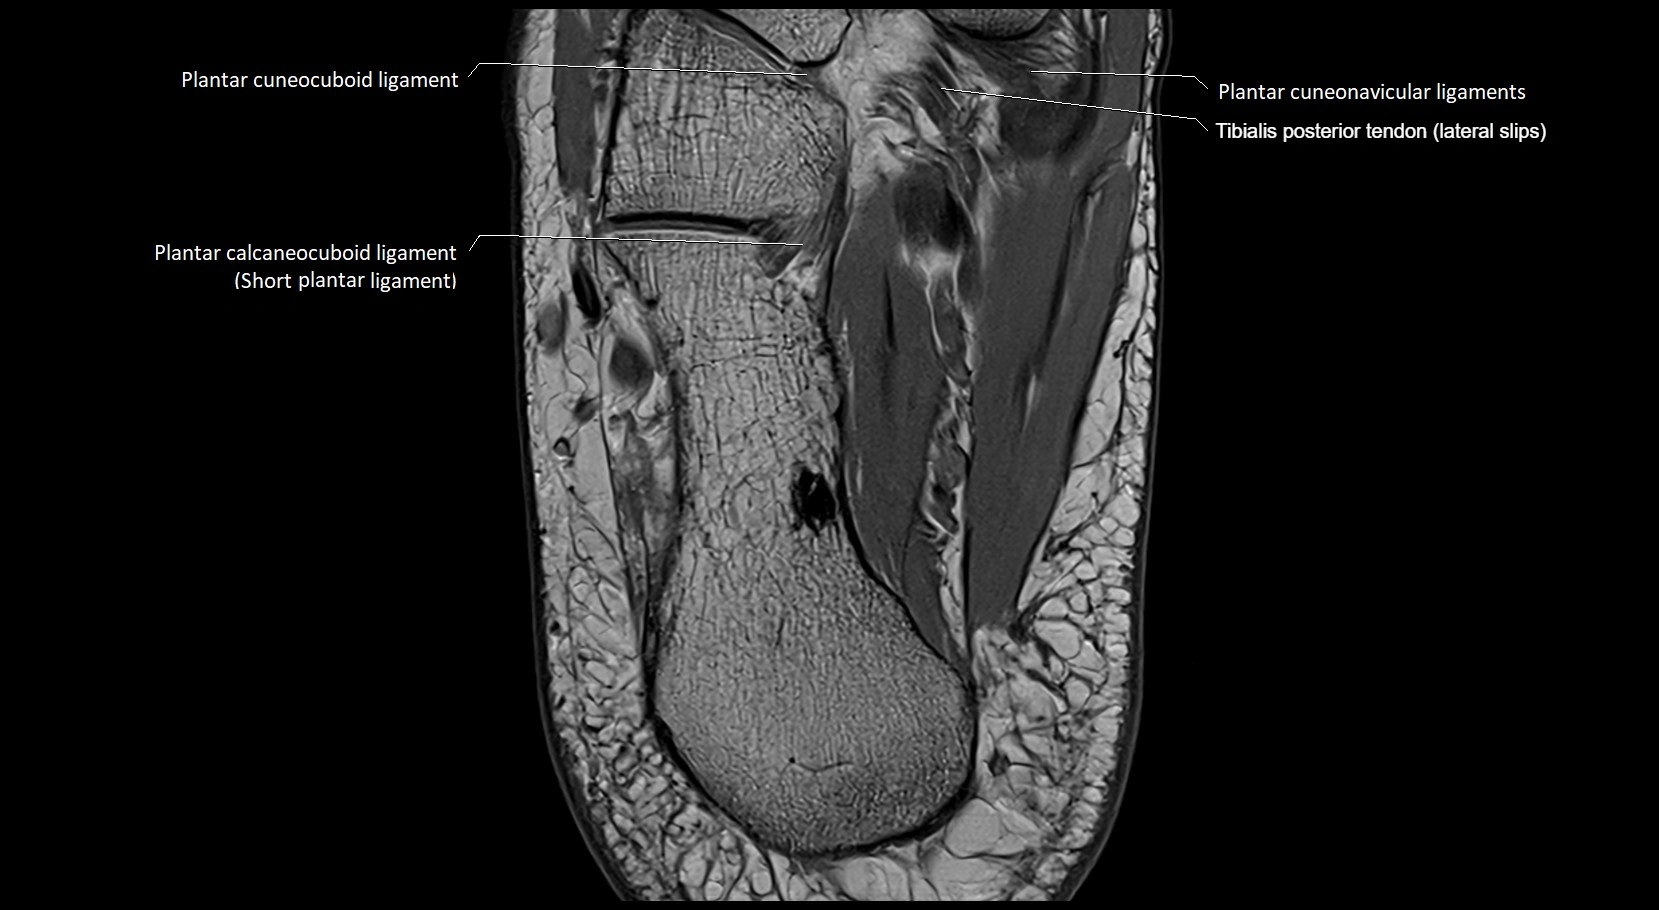

MRI image

image